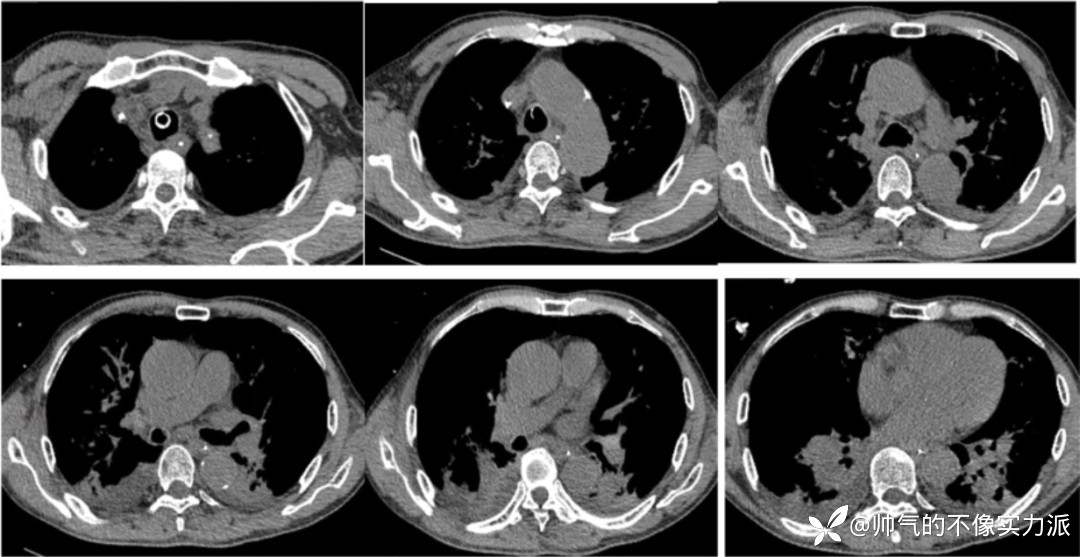

- 与入院前胸部CT相比,患者上肺结节斑片及磨玻璃样渗出影,双侧下肺重力依赖区明显实变影,出现支气管充气征(图2)。

图2 患者胸部CT(2020-12-09)

- 2020年12月12日,复查胸部CT:双上肺磨玻璃影明显增多,下肺重力依赖区依然存在实变影,少量胸腔积液(图3)。

图3 患者胸部CT(2020-12-12)